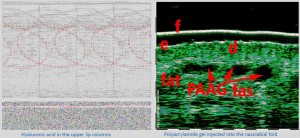

-Έγχυση Πληρωτικών Υλικών (Fillers)